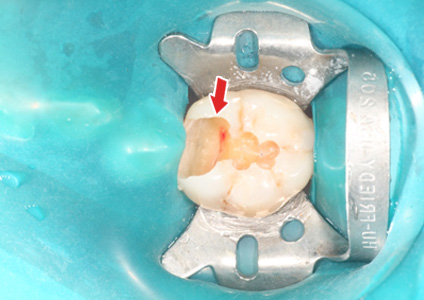

ÃæÄ¡Ä¡·á Áß¿¡ Ä¡¼ö°¡ ³ëÃâµÈ ¸ð½À

2. 2½Å°æÄ¡·á 2.